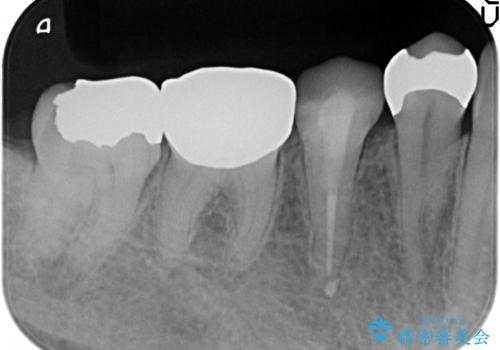

- 右下の奥歯でものを咬むと違和感があるので診て欲しいといらっしゃった方の症例です。

右下6は神経が死んでいたため根管治療を行い、オールセラミッククラウンによる補綴を行いました。

右下7は冷たいものがしみていたため、銀歯を除去後、オールセラミッククラウンによる補綴を行いました。